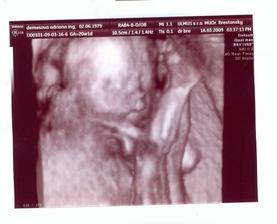

Teraz nás už konečne čaká 3Dčko v pondelok....a hádam budeme vidieť aj čiaročku alebo paličku.

16.3.2009 3D: 20tt+1, a je to tam! čiaročka!!! takže vraj na milión % bude dievčatko. s taťuldom sa neskutočne tešíme na našu bambuľku!